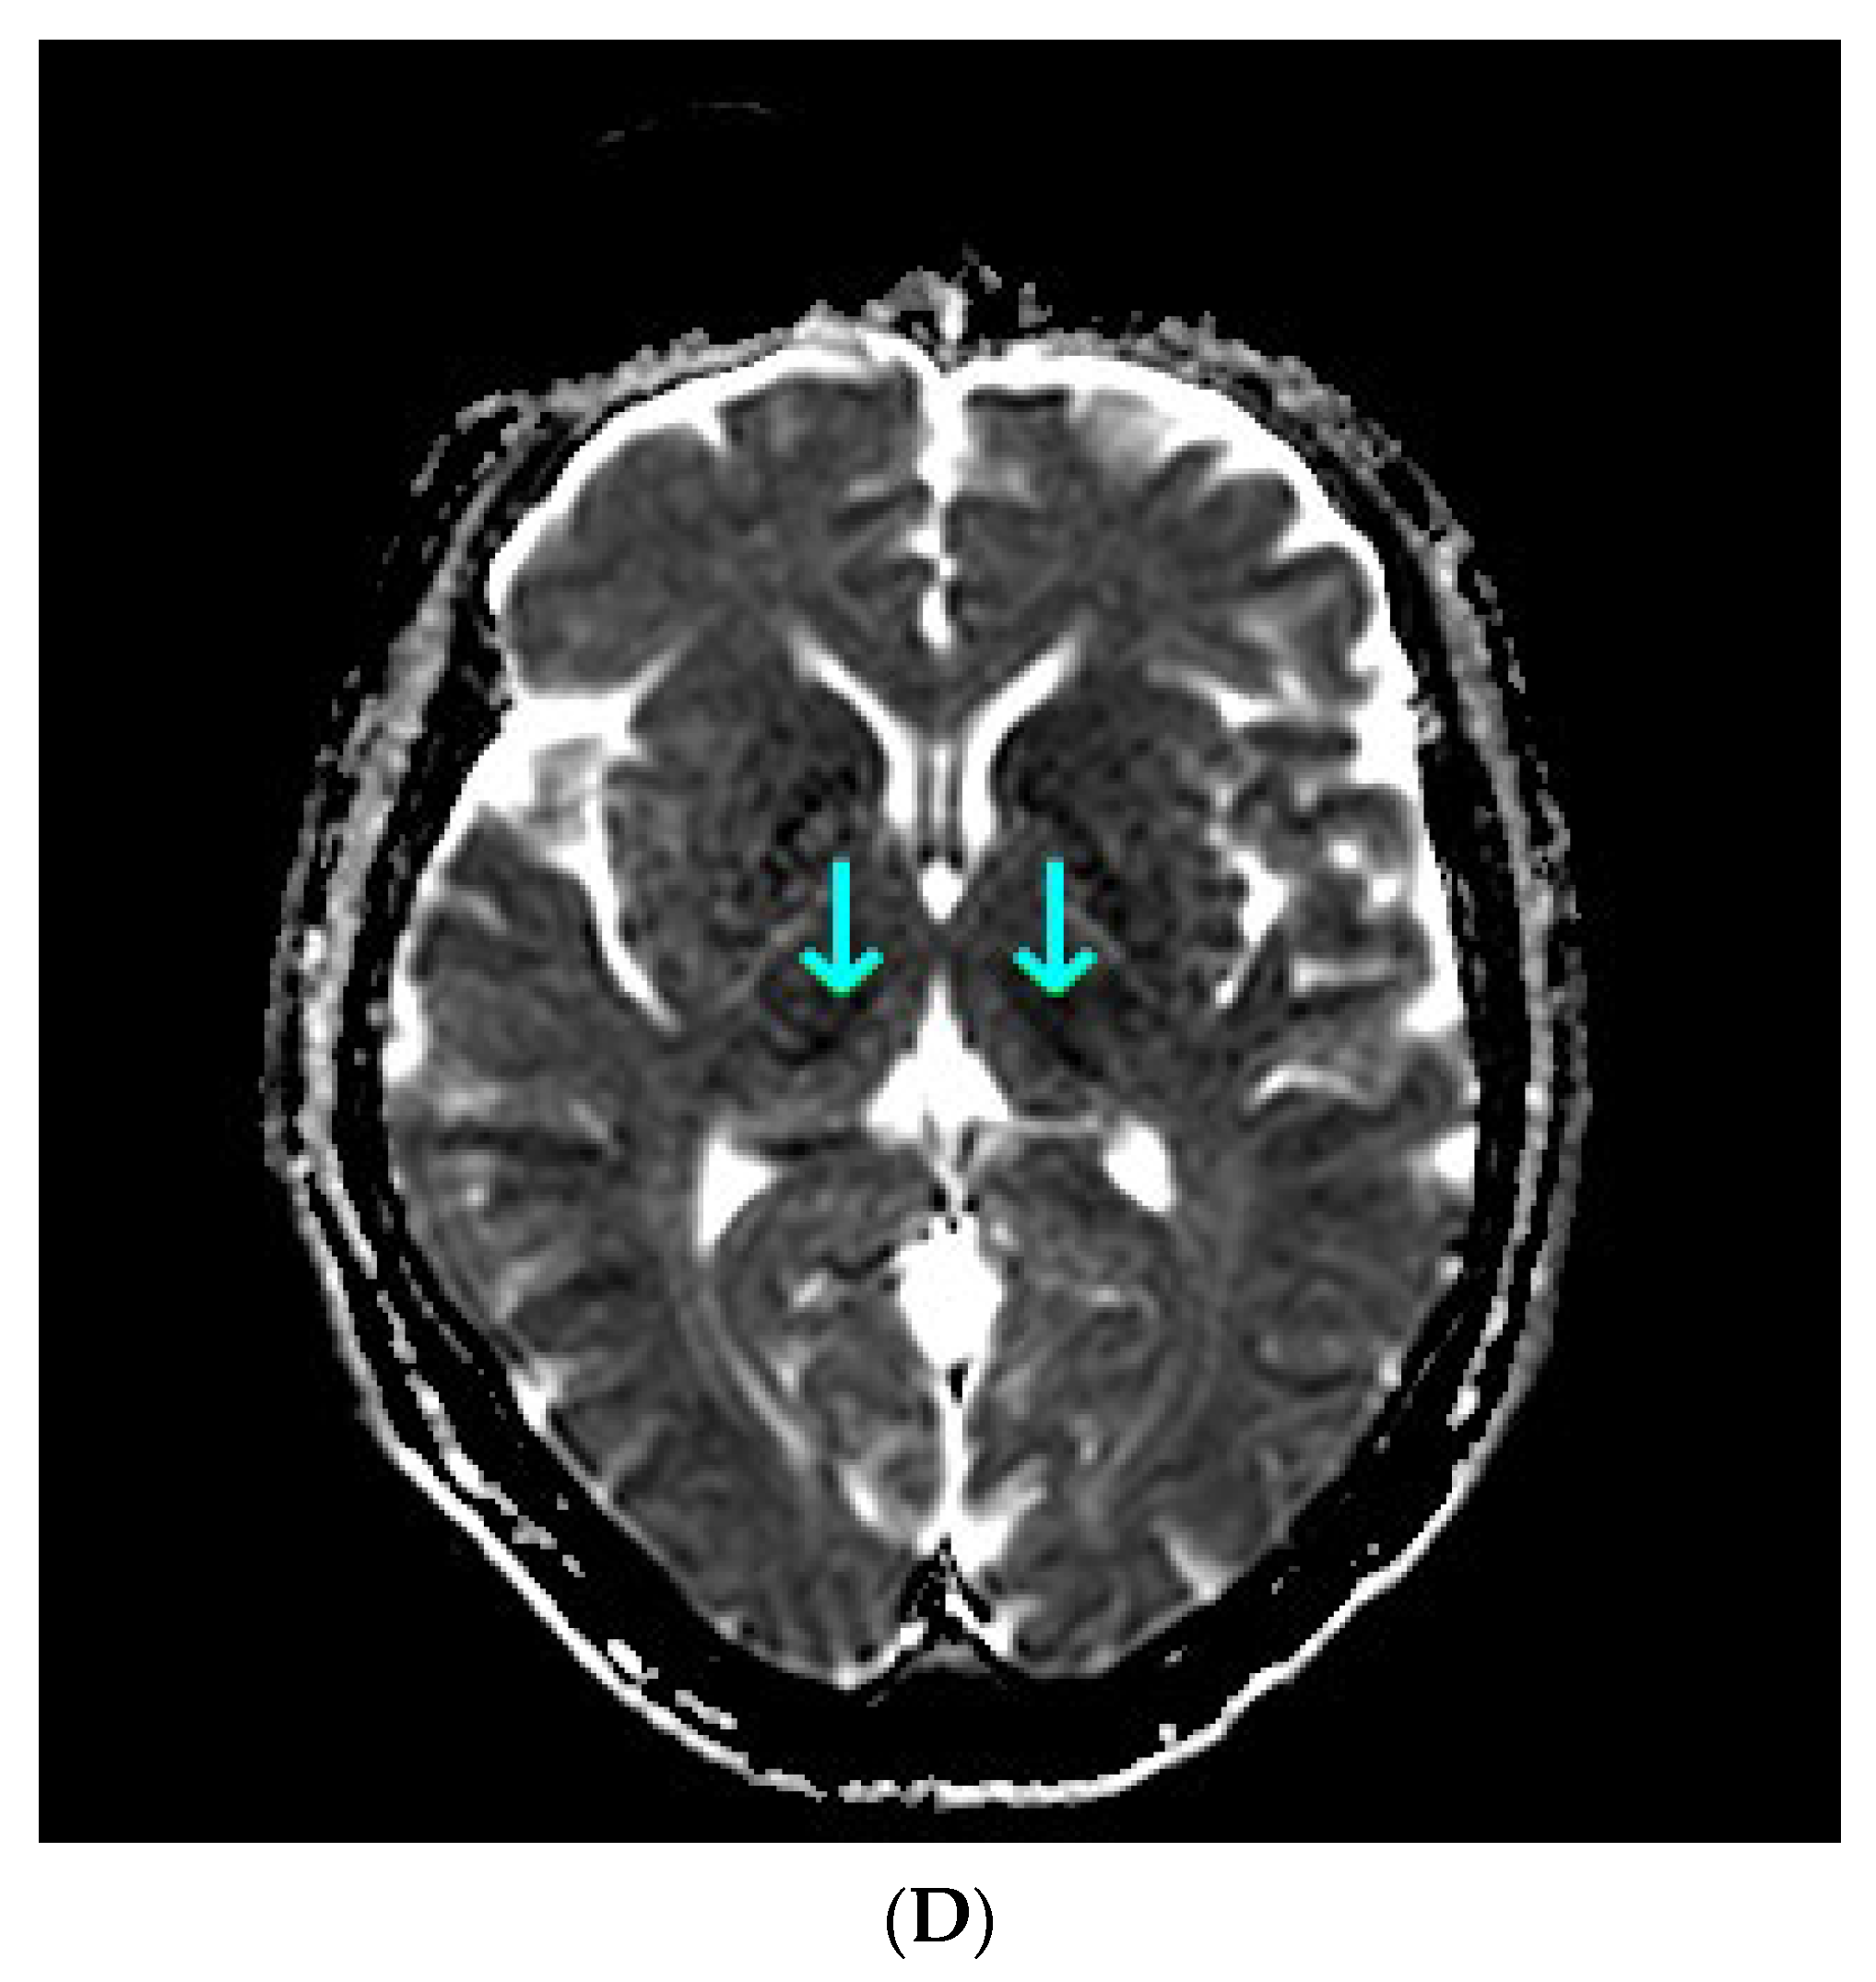

Common causes of decompensation of chronic liver disease include gastrointestinal (GI) bleeding, infection, high alcohol intake and hepatotoxic medications [1]. As the last three were unlikely, urgent esophagogastroduodenoscopy was ordered, however it showed non-bleeding esophageal varices and scarification following previous banding procedures in the middle and lower part of the esophagus. Gastrointestinal bleeding being the most likely cause of chronic liver decompensation was therefore excluded. In order to find the cause of impaired consciousness multimodal diagnostic assessment was initiated. Toxic screen showed absence of phenobarbital, carbamazepine, benzodiazepines, tricyclic antidepressants; valproic acid was present in the subtherapeutic concentration of 41 µg/mL (therapeutic range 50–100 µg/mL). On day 3 of ICU hospitalization angio-CT of the head was performed and also revealed no abnormalities. The EEG showed no signs of epileptiform activity, although generalized inhibition of basal activity was present. The direct chemiluminescence of the cerebrospinal fluid (CSF) performed on day 4 showed absence of IgG and IgM against B. burgdorferii, Herpes simplex virus, and cytomegalovirus. There was no DNA of Ebstein-Barr virus detected in the CSF sample. The onco- and anti-neuronal immunoglobulin panel performed with indirect immunofluorescence was negative: anty-Amp, anty-Cv2.1, anty-PNM2/Ta (Ma2/Ta), anty-Ri, anty-Yo, anty-Hu, anti-Rec, anti-SOX1, anti-titin. The anti-neuronal screen performed with indirect immunofluorescence was negative: anty-AMPA (GluR1/GluR2), anty-GABA B, anty-NMDA, anty-DPPX, anty-CASPR 2, anty-LGl 1). All initial microbiology cultures (blood, aspirate, urine, CSF) were negative. As part of diagnostic assessment the magnetic resonance imaging (MRI) examination of the head was performed on day 5. The image obtained by MRI is depicted in Figure 1A–D.

Figure 1.

(A) Magnetic resonance imaging of the head. T1 Spin Echo, axial. Green arrows point to hyper-intense globi pallidi; (B) Magnetic resonance imaging of the head. T2 Turbo Spin Echo Dark-fluid. Red single arrows point to the mild symmetric hyper-intensity in the insulas; double red arrow point to the pronounced hyper-intensity in the left occipital lobe; (C) Magnetic resonance imaging of the head. Diffusion Weighted Imaging b = 1000, axial. Cyan arrows point to the restricted water diffusion in both thalami; (D) Magnetic resonance imaging of the head. Apparent Diffusion Coefficient, b = 0, b = 1000, axial. Cyan arrows point to the restricted water diffusion in both thalami.

Taking into account clinical picture the differential diagnosis involved: chronic liver encephalopathy, acquired hepatocerebral degeneration (AHD), acute liver encephalopathy. Various nonspecific, not limited to vascular supply region, lesions of the brain, including rare appearance like T1 gray matter hyper-intensity, were consistent with hepatic encephalopathy. Because liver encephalopathy was a possible diagnosis, ammonia concentration was determined. The ammonia concentration determined with spectrophotometry reached 417 µg/dL, highly above the reference range (31–123 µg/dL). Ammonia was found to be an independent risk factor for hepatic encephalopathy and intracranial hypertension, the latter occurring in 55% of patients with ammonia concentrations >200 μmol/L (340.6 µg/dL) [2].